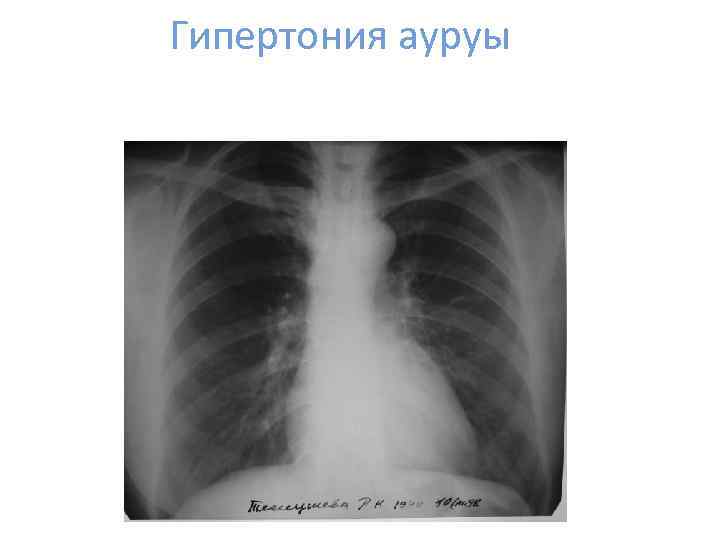

Гипертония ауруы